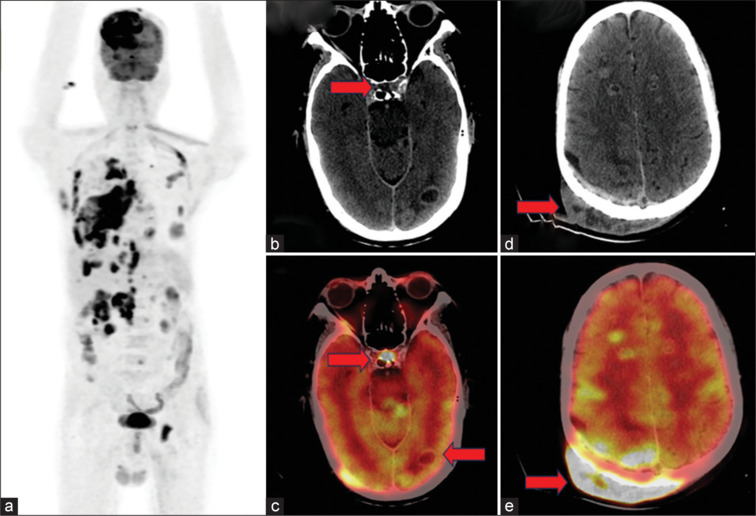

Metastases from squamous cell carcinoma of the lung typically occur in the brain, liver, adrenal glands, bone, and regional lymph nodes. It is exceedingly uncommon to encounter multiple rare sites of metastasis from a single primary neoplasm. Herein, we describe a case of a 44-year-old male diagnosed with squamous cell carcinoma lung with pituitary and renal metastasis detected on 18F-FDG (Fluorodeoxyglucose) PET/CT. 18F-FDG PET/CT is the standard of care and is an integral part of the clinical staging of patients with lung cancer. According to published literature, the incidence of symptomatic pituitary and renal metastasis from squamous cell carcinoma lung is rare to find with incidences <1% and 5%, respectively. The revelation of rare sites of metastasis originating from primary squamous cell carcinoma lung, as reported in this case on FDG PET/CT, illuminates the exceptional rarity and intricacies in oncology. The exquisite sensitivity of FDG PET/CT enables the identification of occult metastasis in atypical anatomical locations, presenting a distinct advantage over conventional imaging modalities.